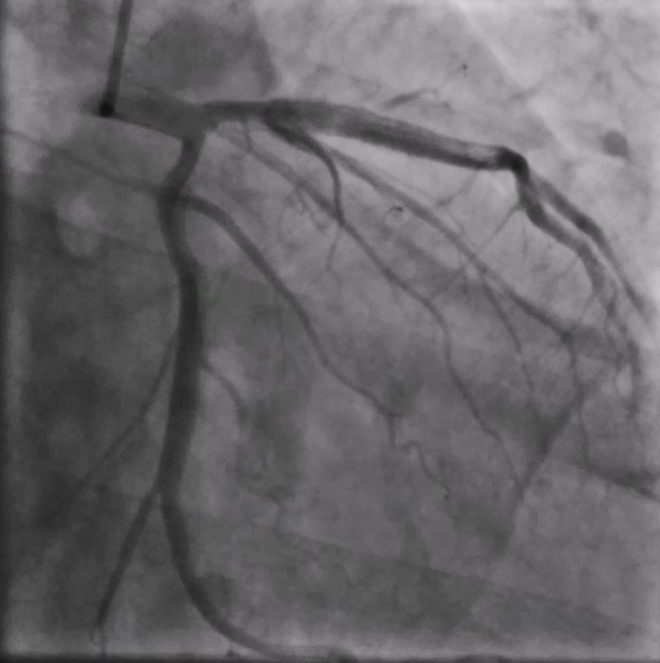

重庆江北区的65岁李先生反复心前区疼痛2年,半年前在外院前降支近端植入支架一枚,术后症状仍然反复,曾在多家医院就诊,无法明确原因。近日到新桥医院就诊,医院心血管内科为李先生安排了冠脉造影检查,结果提示:前降支支架内未见明显狭窄,但血流速度较正常冠脉明显变慢。

引起血流慢的原因何在?

二维平面的造影结果不能提供更多的信息,于是,新桥医院导管室主任赵晓辉教授决定采用高清IVUS技术(HD-IVUS,high definitionIntravascular ultrasound)对冠脉内结构进一步分析。结果显示支架梁近端开口处有一低密度斑块是引起慢血流的罪魁祸首。